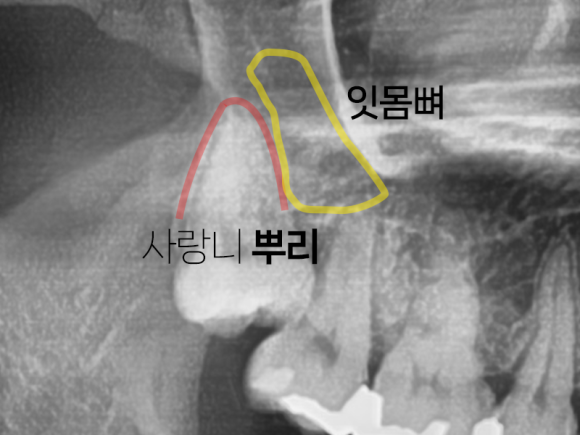

첫 번째는 사랑니 뿌리의 완성도를

살펴봐야 합니다.

사랑니의 뿌리는 20대 초중반에

완전히 형성됩니다.

뿌리가 완전히 형성되기 전이나

혹은 덜 형성되기 전에 발치를 하면

뼈조직도 유연하고

사랑니의 뼈가 상악동이나 하치조 신경관과의 거리에

닿기 전이라서 비교적 발치가 쉬운 경우가 많습니다.

이해를 돕기 위한 사진입니다.

나이가 들수록 잇몸뼈의 밀도는

점점 더 단단해집니다.

그 말인즉슨, 치아의 뿌리와 잇몸뼈와의

유착이 강해진다는 것을 의미하죠.

따라서 나이가 들어 사랑니를 발치하려고 하면

잇몸뼈와 사랑니 뿌리가 너무 강하게 유착되어

발치 시 더 큰 힘을 필요로 하는 경우가 많습니다.

심지어는 사랑니가 잘 빠지지 않아

조각내어 발치를 해야 하는 경우도 있습니다.

따라서 잇몸뼈와 사랑니가

강하게 유착되기 전에 발치를 하는 것을 권장 드립니다.